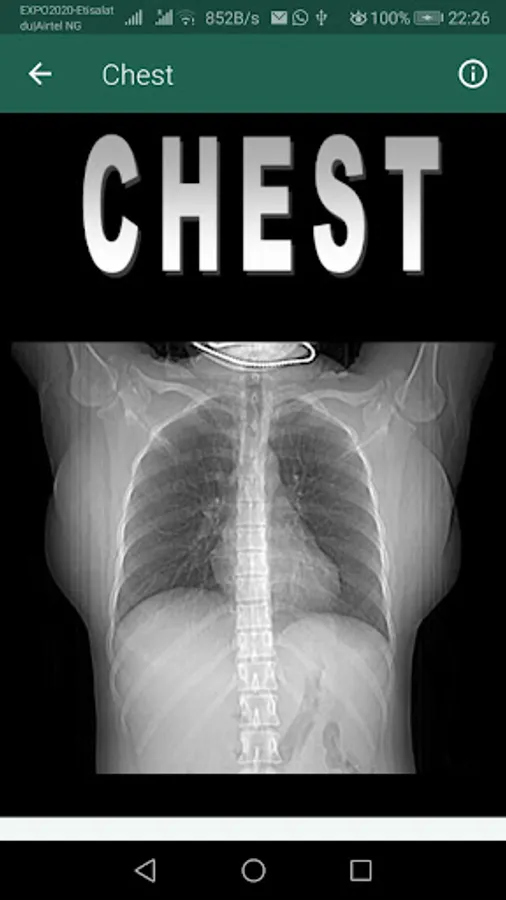

CT or MR images of special interest are featured on the opening page in each chapter to pique readers’ interest in the area about to be covered in the App.